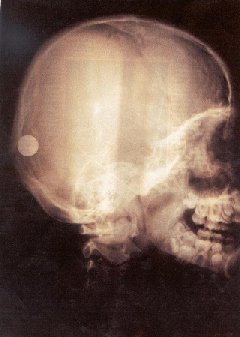

They easily pass through soft body

tissues, but they are somewhat blocked by hard material

like bones.

X-ray of a person's head

X-rays are almost completely stopped by

Thus, if a beam of x-rays passes through

your body and exposes some film, a faint outline of your

soft tissues will be seen, but your bones will show up

distinctly. If a sheet of lead was put between the

source of the x-rays and the film, it would not be

exposed.